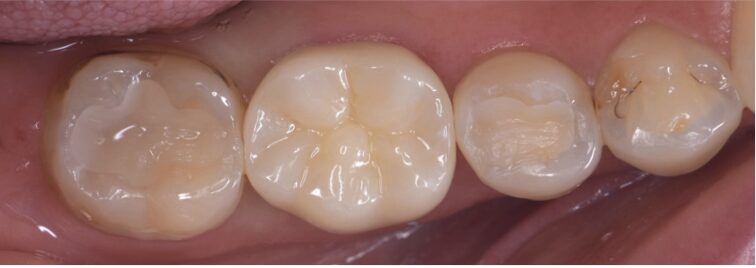

After

| 治療内容 | 根管治療 セラミッククラウン |

| 治療期間・治療回数 | 5回 |

| 治療費用 | 148500円(税込) |

| 備考 | 30代 男性 |